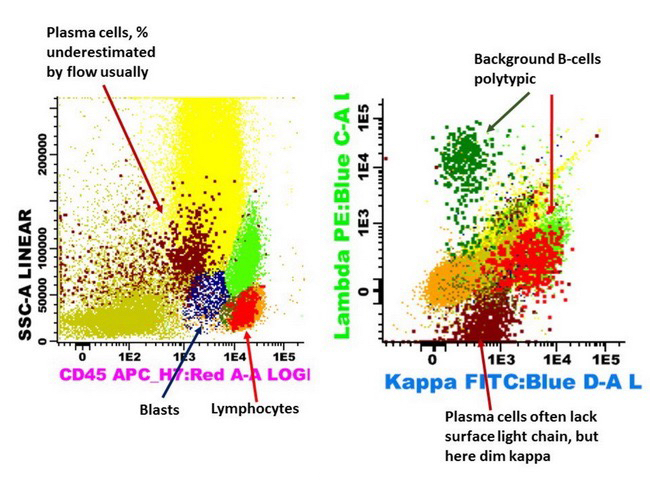

Flow cytometry description

- Monotypic cytoplasmic Ig and usually lack surface light chain

- Express CD38, CD138, often CD56+ or CD117+; may have partial CD45, usually negative for CD20, CD19 and CD10 (Cytometry B Clin Cytom 2016;90:61)

- Exception in myeloma with t(11:14) where plasma cells more often express B cell markers including CD19 and CD20